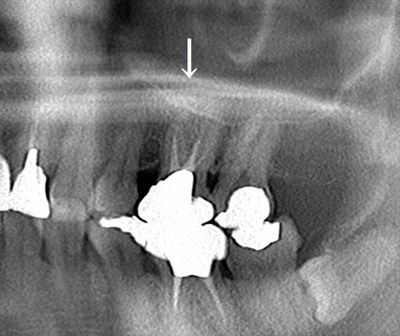

矢印の左上第一大臼歯の金属を除去して再根管治療を行います。